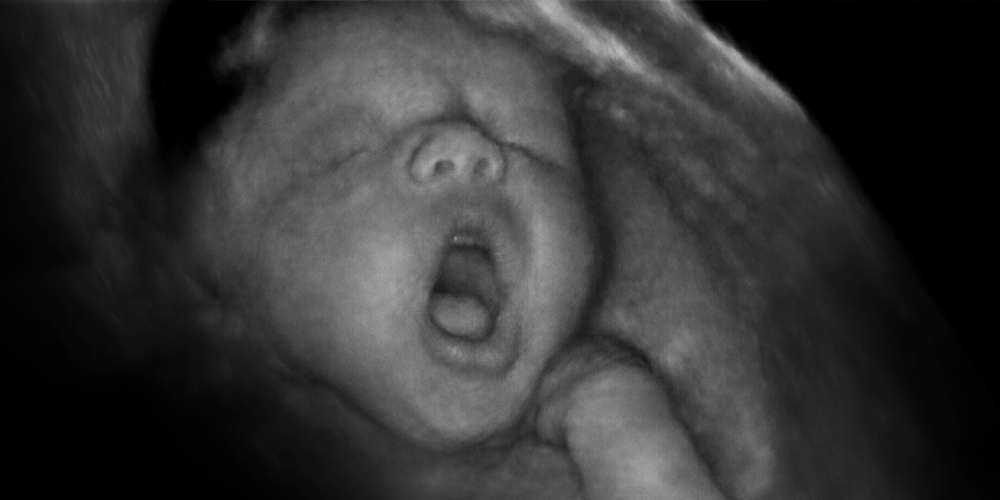

Gebelik boyunca tek bir kez bebeğin ultrason muayenesi yapılacak olsa en uygun hafta 22.inci haftadır. Daha doğrusu 20-22 haftalar arası... Nedeni anomalilerin anlaşılabilmesi açısında, bebeklerin epeyce büyümüş olmaları bir avantaj. Öte yandan ağır bir anomali görürsek gebeliği sonlandırabilmek için üst sınır olarak kabul edilen 24.üncü hafta üst sınırının geçilmemiş olması...

Yani ne erken ne geç, tam zamanı...